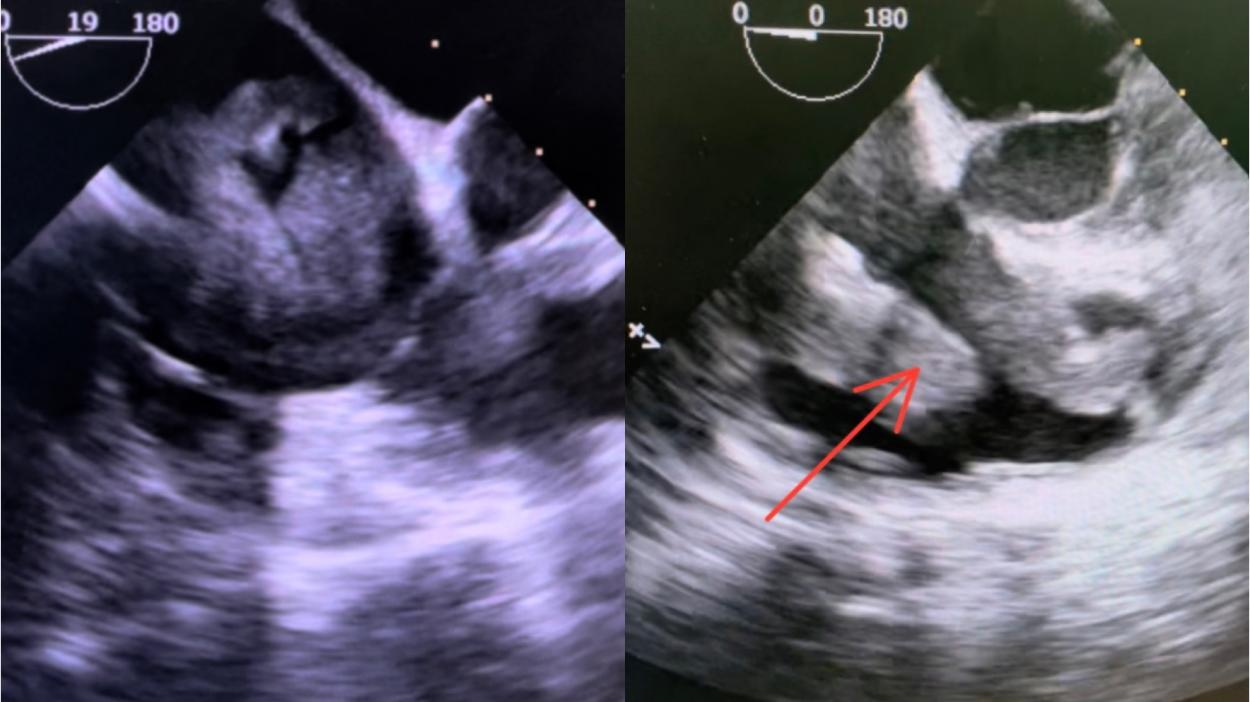

术中TEE所见